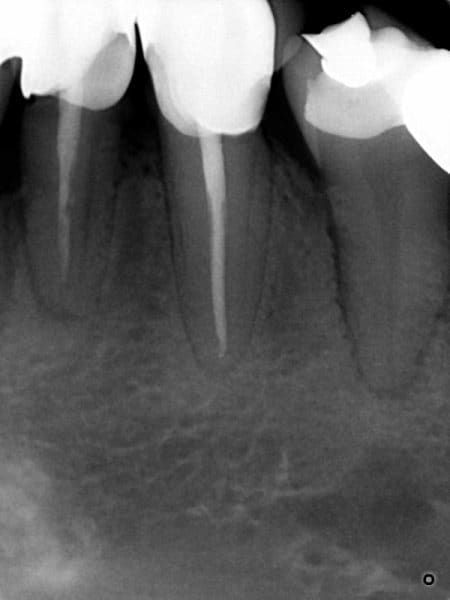

Patiente nouvelle. 38 ans. consulte pour douleur moyenne et gonflement léger au niveau de la 34. A la percussion, la 34 est la seule à réagir de façon modérée.

A j+2, bel abcès qui suppure au collet de la 34. Je fraise en direction de la chambre, douleur, a l'ouverture de la chambre, douleur plus intense, j'attends................rien, pas de collection purulente mais une pulpe bien vivace.

Grosse voussure en vestibulaire de la 34 qui lui déforme un peu le visage. la 34 n'est pas mobile et à peine douloureuse à la percussion.Ça n'évoque pas un abcès paro.

C'est situé plutôt en vestibulaire, antérieur /34, pas de gonflement en regard de 35. La 36 est asymptomatique et le fond du vestibule non douloureux.

Je la reverrai juste pour faire l'endo de la 34 suite à mon erreur de diagnostic (pas très fière sur ce coup là, d'un autre côté elle était pas trop vivace quand même...)